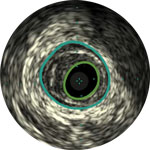

The Visions PV .035 digital IVUS catheter with 60mm imaging diameter evaluates vascular morphology in blood vessels and provides cross-sectional imaging of these vessels.

Angiography provides information on luminal characteristics of peripheral arteries, but severely underestimates the extent of atherosclerosis in patients with PAD, even in “normal appearing” vessels.1

Guides device sizing to ensure precise wall apposition, drug delivery, and placement

Understand plaque type and severity to help guide proper device selection

Visualize plaque burden location for precise treatment

Confirm true lumen or sub-intimal guidewire location